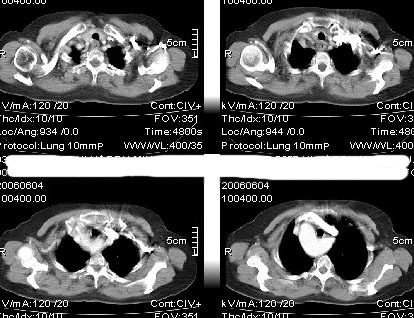

先天发育异常:降主动脉位右侧,主动脉弓形态欠规整。余未见异常影像。

主a弓及降主a都位于右侧,近膈肌时位于椎体前,,左室流出道及其他结构未见明显异常

右位主动脉弓伴迷走左锁骨下动脉。

楼主发布的是右主动脉弓的由中动脉弓并迷走左锁骨下动脉,并不是5楼战友说的全反位。

谢谢各位战友的提示,说实话我除看到主动脉右位外。我还真没想到是左锁骨下动脉{我把它认为是左头臂静脉了}!!!在次谢谢各位战友。